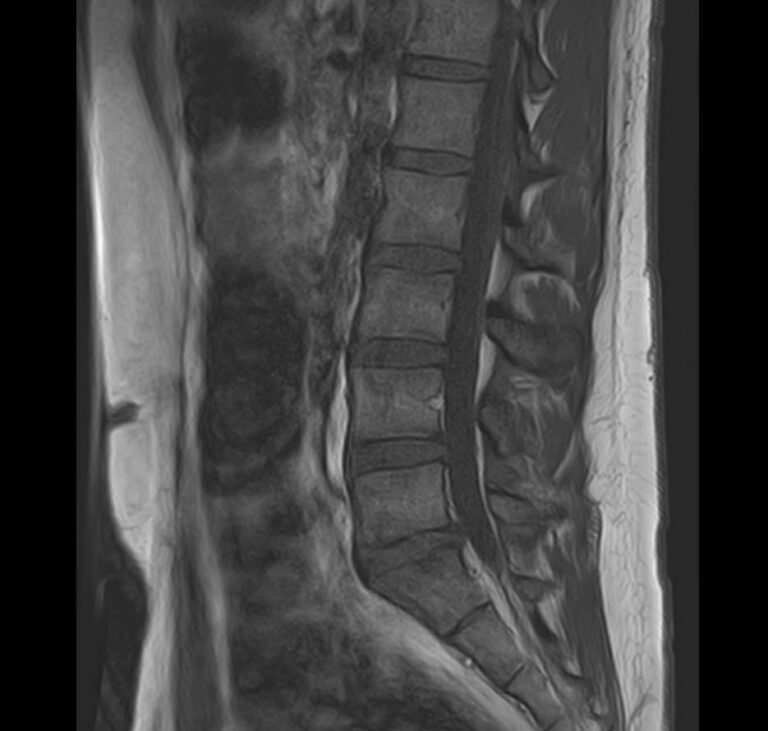

• Дегенеративные-дистрофические заболевания в шейном, грудном, пояснично-крестцовом отделах позвоночника и копчике (спондилез, спондилоартроз, остеохондроз).

• Грыжи межпозвонковых дисков (протрузии, экструзии).

• Стеноз (сужение) позвоночного канала.

• Патологические изгибы позвоночника, сколиоз, усиленный или выпрямленный лордоз как нарушение статической функции позвоночника.